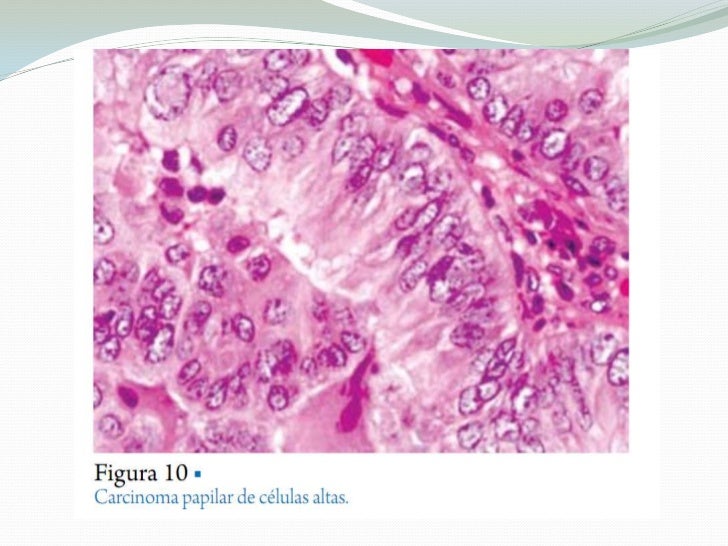

Carcinoma papilar de tiroides